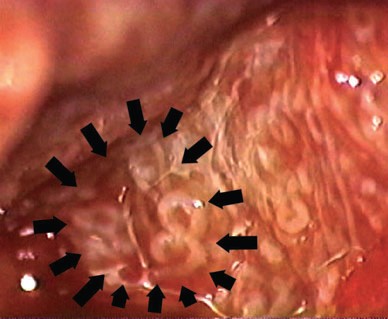

Şekil-1: Mikro-TESE işleminde mikroskop altında sperm içeren genişlemiş sperm kanallarının görünümü.